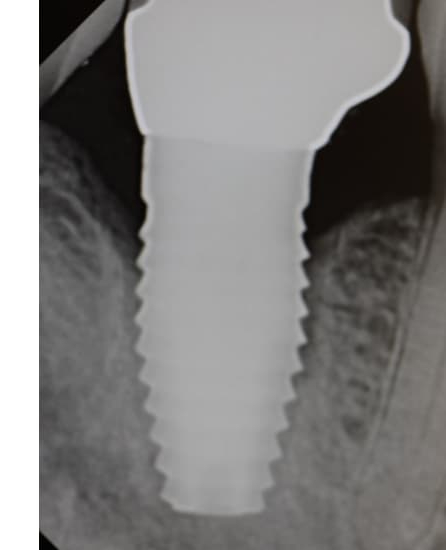

A new paper evaluated Laser-Lok Dental Implants over a 20-year period and concluded that these dental implants showed high cumulative survival rate and low rates of marginal bone loss.